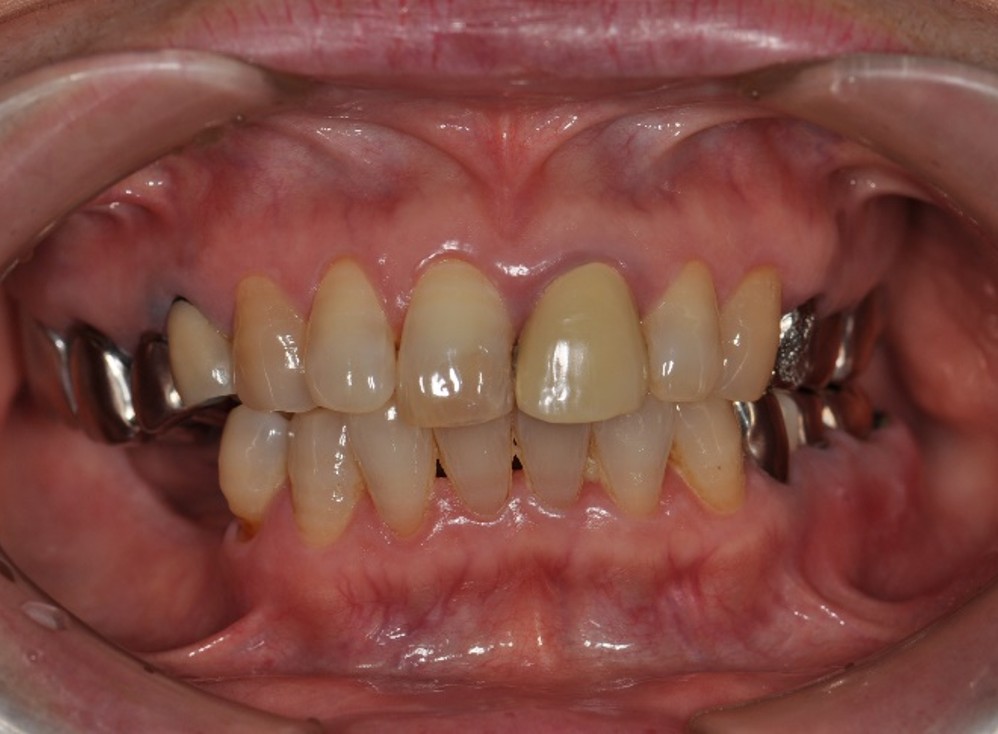

治療前